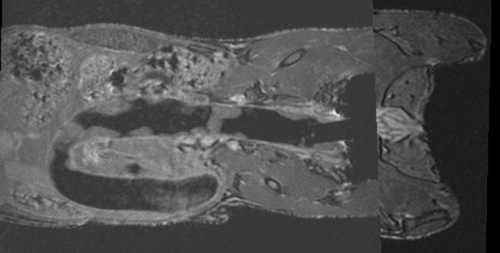

v3.6.1 Slicer3-6Announcement-v1.png Slicer Registration Library Case #35: Mouse Colon Brain MRI

case A lleft case B

fixed image 1/target

MRI mouse 1

moving image

MRI mouse 2

• reference/fixed MRI: 0.12 x 0.12 x 0.1 mm, 512 x 512 x 94

• moving MRI: 0.09 x 0.09 x 0.1 mm, 512 x 512 x 94